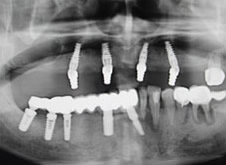

2016年6月10日,即刻负重种植牙案例将震撼来袭!国际口腔种植医师协会深圳分会会长、深圳市二院原口腔科主任、麦芽口腔总院长郑苍尚教授、有近万成功种植案例、麦芽口腔中方院长游勤波携手先进团队即拔即种即刻负重高感度种植牙手术,千位缺牙市民将共同见证失牙修复奇迹!对于缺失牙市民来讲,这将是一次不可错过的种植牙课堂!

此次种牙直播手术是牙槽骨萎缩严重,即刻负重高难度种植牙手术,在技术上将实现全面升级!麦芽口腔始终提倡并专注于亚洲口腔医学技术研究和创新的数字化口腔诊疗机构,根据亚洲人骨骼与欧美人骨骼的差异性,历经多年的不断摸索、实践、总结精研而成的,被称之为较适合亚洲人的种植牙技术。国际口腔种植医师协会深圳分会会长、深圳市二院原口腔科主任、麦芽口腔总院长郑苍尚教授介绍,此次手术直播将采用目前全球公认的、较先进的牙齿种植技术——即刻负重技术!

殷先生的牙齿状况比较特殊:上排牙骨比下排本身就窄,上牙槽骨还缺牙30多年,废用性萎缩非常严重。此前预约了很多口腔医院,普通的种植牙技术恐怕很难实现上面半口种植,并且在咬合和美观度方面也无法达到预期效果!郑苍尚院长综合考虑目前牙齿具体情况为殷先生推荐all-on-4(种植4颗即能恢复半口牙)手术方案......